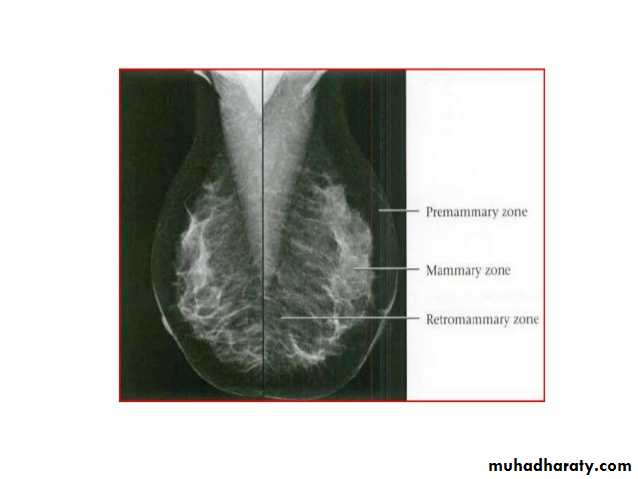

Breast density & who can U detect a mass lesionYour mammogram report must take in consideration & assessment the breast density. Breast density is based on how fibrous and glandular tissue tissues are distributed in your breast, vs. how much of your breast is made up fatty tissue.

Dense breasts are not abnormal, but they are linked to a higher risk of breast cancer. We know that dense breast tissue can make it harder to find cancers on a mammogram. Still experts do not agree what other tests, if any, should be done in addition to mammograms in women with dense breasts who aren’t in a high-risk group (based on gene mutations, breast cancer in the family, or other factors